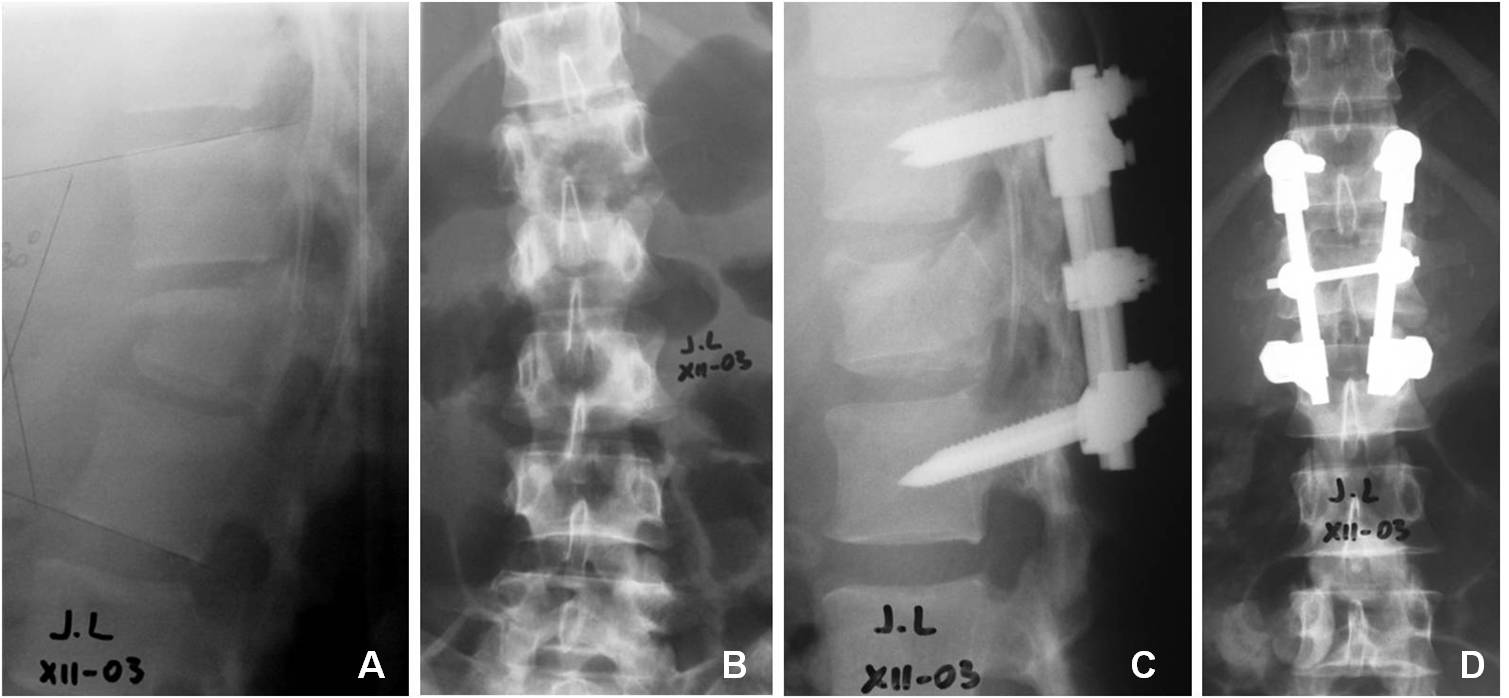

Evaluación clínica y radiológica de la instrumentación y artrodesis corta por vía posterior en fracturas toracolumbares. [Posterior arthrodesis and short instrumentation in thoracolumbar spine fracture:clinical and radiological evaluation]

33. Petracchi M, Gruenberg M, Solá C, Ortolán E. Fracturas por estallido en columna dorsolumbar instrumentadas con tornillos

pediculares. Rev Asoc Arg Ortop Traumatol 2003; 68(4): 273-83.

34. Baños Clemente A, Ramirez Villaescusa J, Martinez Castroverde J, Martinez Arnaiz E, Andreés Gonzalez JM. Tratamiento

quirúrgico de fracturas toracolumbares por vía posterior con instrumentación y fusión bisegmentaria. Rev Esp Traumatol 2002;

37(210):84-88.

35. Parker JW. Successful short-segment instrumentation and fusion of thoracolumbar spine fracture. Spine 2000;25(9):1157-69.